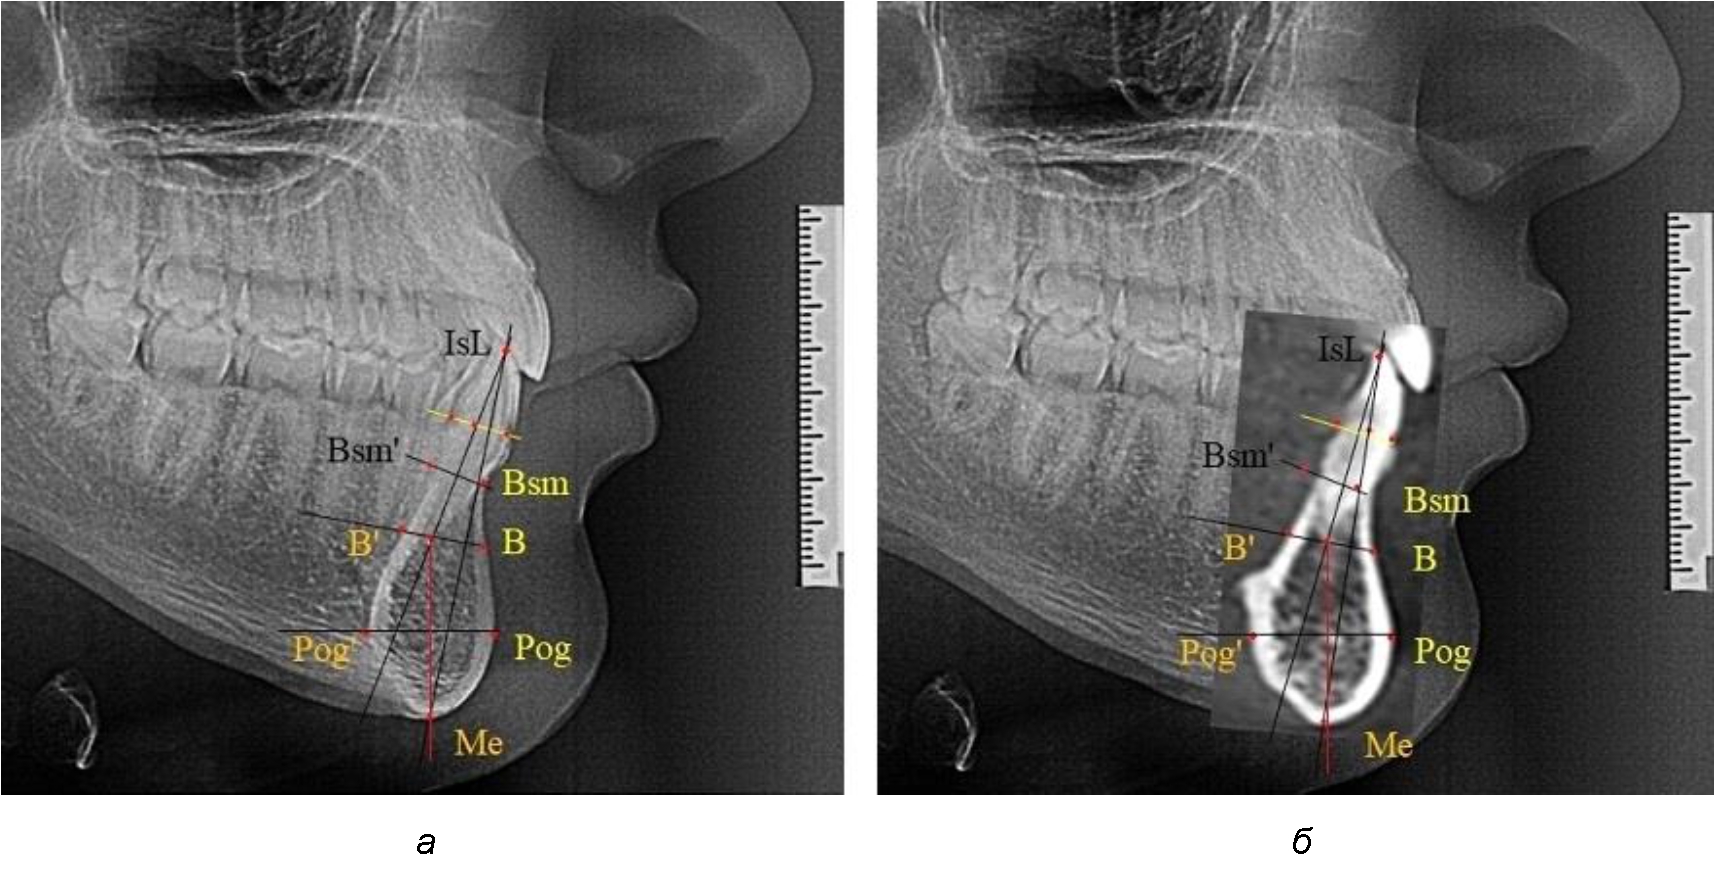

При анализе боковых телерентгенограмм использовали фрагменты гнатической части, на которых оценивали вертикальные и сагиттальные параметры резцового нижнечелюстного сегмента, на который наносили те же ориентиры, что и при анализе нативных препаратов и их рентгенограмм.

При необходимости и/или возможности проведения КЛКТ-исследования проводили анализ с сопоставлением фрагмента, что повышало точность диагностических мероприятий (рис. 2).

Рис. 2. Фрагменты ТРГ с ориентирами для измерения параметров резцового сегмента (а) и с наложением фрагмента КЛКТ (б)